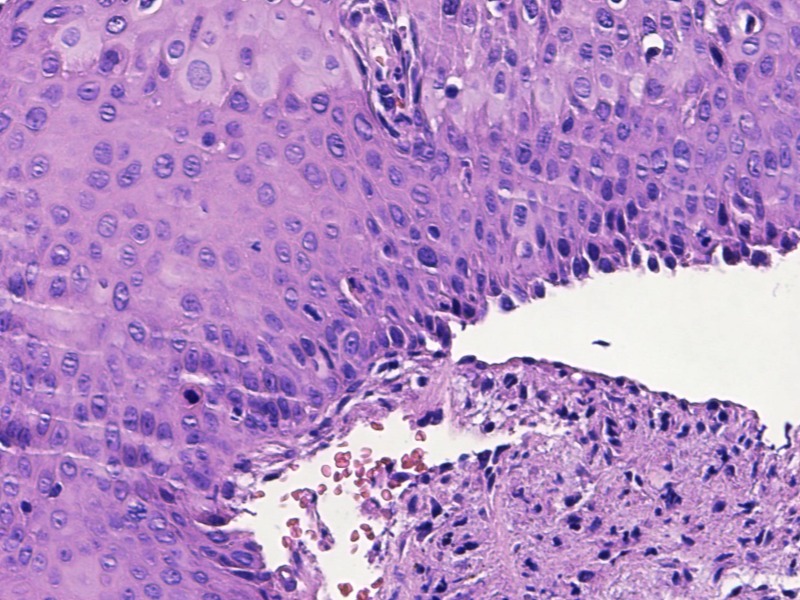

宫颈活检高级别?

TCT:ASC-US HPV:52+

宫颈活检

1、宫颈活检:灰白组织9块,直径0.3-0.5cm,质软,全取包。

图3

LSIL。

基底样细胞没有那么多,低级别够了